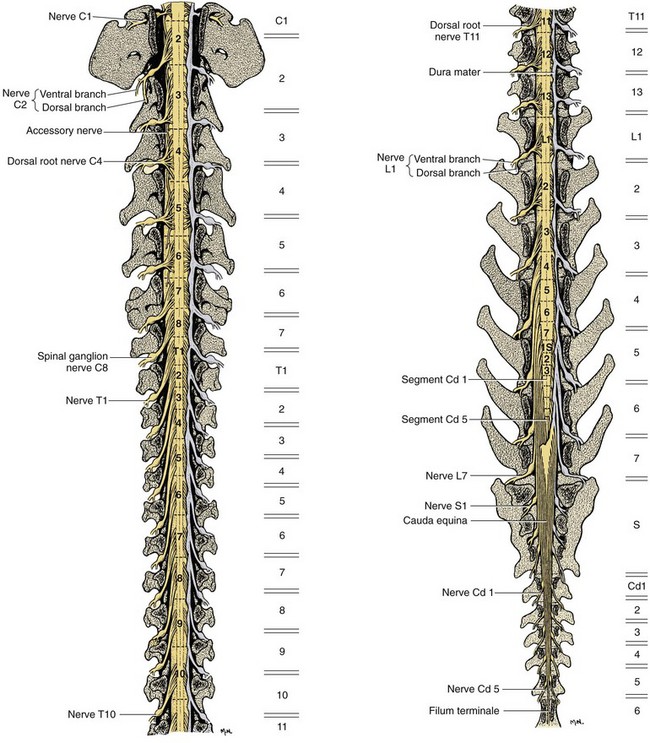

Anatomy of Spinal Cord Injury – Treatment, Complication – Rxharun

What is a Spinal Cord Injury (SCI)? – First Aid for Free

Diagram | Spinal Cord Injury | Pinterest | Spinal Cord Injury and Cords

Diagram showing the relationship between spinal nerve roots and …